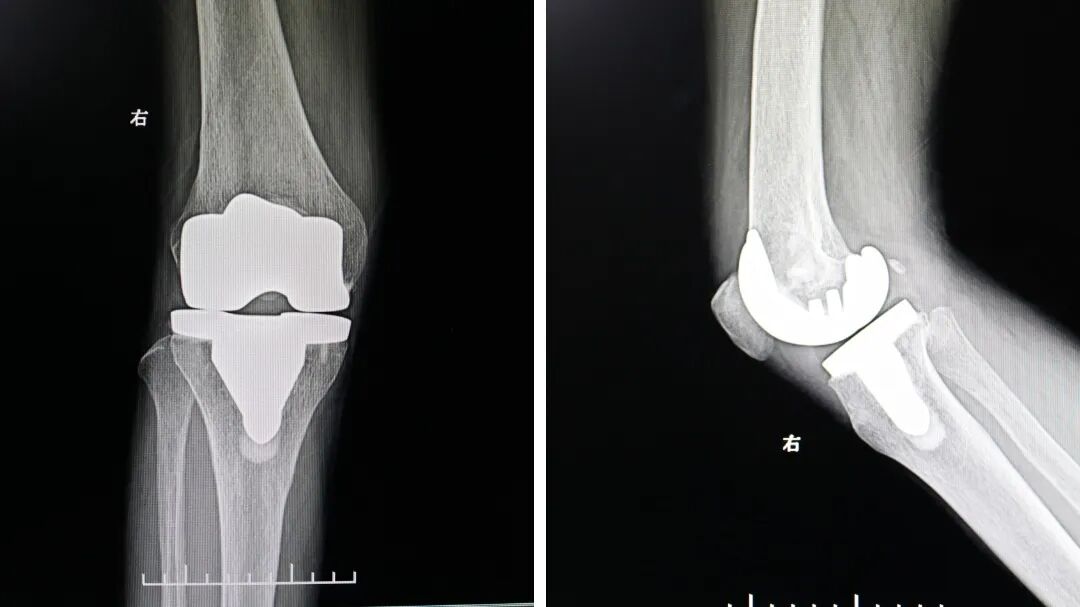

上周我们就遇到了这样一位亟需关节置换的患者,她右膝关节疼痛10多年,平时也只是贴贴膏药,吃吃药,近半年来,右膝疼痛加重,平地行走也变得很困难,来到我院后,我们发现患者双膝关节呈明显外翻畸形,右膝不能完全伸直,被诊断为:右膝重度类风湿性关节炎伴屈曲外翻畸形。

患病时间太长、右膝关节严重外翻畸形、膝关节间隙变窄、消失,外侧平台骨破坏明显,我们详细评估后确定保守治疗难见疗效,关节置换手术是最优选择。三天后,我们手术团队密切配合为她顺利完成了人工膝关节置换术。

膝关节置换,换掉的是什么?很多人害怕做膝关节置换手术,是因为他们误以为手术是把整个膝盖都换掉,事实上创伤并没有想象中那么大。在膝关节置换术中,并不是把膝关节全换掉,而是只换掉膝关节被破坏的关节面,相当于膝关节的一个“零部件”。换掉的部分会被替换成人工假体,以恢复膝关节的正常功能。